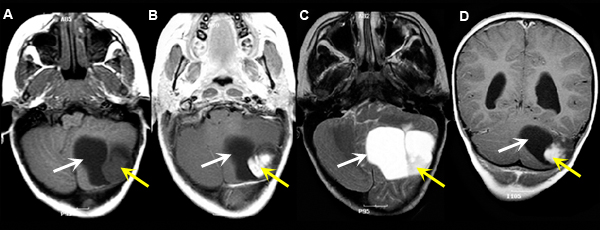

Figure 4

A: Pre-contrast axial T1 wtd. MRI

B: Post-contrast axial T1 wtd. MRI

C: Axial T2 wtd. MRI

D: Post-contrast coronal T1 wtd. MRI |

Imaging findings: Figure 4

-

Left cerebellar hemispheric Pilocytic Astrocytoma with an enhancing mural nodule (yellow arrow in figs B, D) and a cystic component (white arrow).

White arrow in all the images points to the cystic component and yellow arrow to the mural nodule.

Final impression:

Pilocystic Astrocytoma

Pilocystic Astrocytoma is a primary brain neoplasm occurs most often in children and young adults. It is a slow growing tumor with a solid and cystic component. The solid component is well circumscribed and enhances with contrast.